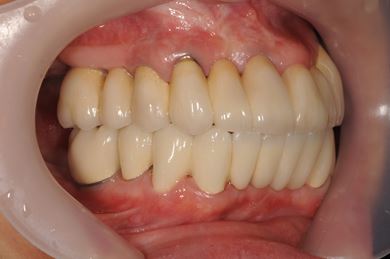

骨再生スピードインプラント治療+セラミック治療

| 性別/年齢 | 女性 / 43歳 | ||||||||||||||||||||||||||||||||

| 主訴 | 骨が薄いが、インプラント治療を希望。 | ||||||||||||||||||||||||||||||||

| 治療方針 | 抜歯と同時にインプラントを埋入し、治療期間を短縮する。ソケットリフトにて上顎洞を拳上し、インプラント治療を可能にする。 | ||||||||||||||||||||||||||||||||

| 治療内容 | インプラント9本(抜歯即日スピードインプラント、ソケットリフト、テンポラリーインプラント+仮歯)、メタルボンドセラミッククラウン18本、メタルボンドセラミックブリッジ6本(メタルボンド用土台6本)、遊離歯肉移植術 | ||||||||||||||||||||||||||||||||

| 総治療費 | 6,282,150円 | ||||||||||||||||||||||||||||||||

| 治療期間 | 1年8ヶ月 |